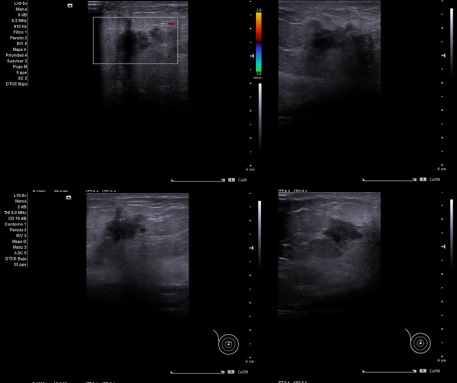

Caso 1: Imagen anecoica de 25 x 30 x 25, que deja refuerzo posterior, sin captar doppler compatible con Quiste mamario.

Caso 1: Quiste mamario.

Diagnóstico diferencial: Fibroadenoma de mama.